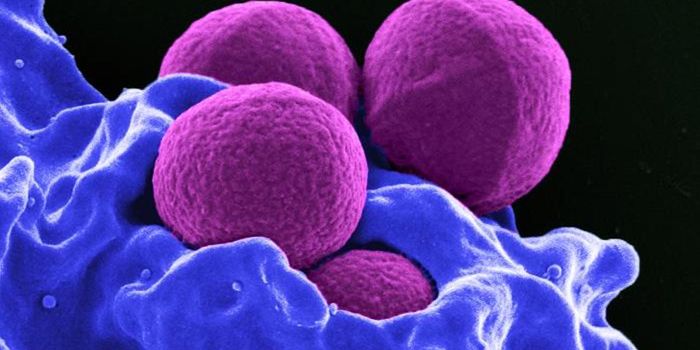

AUG 23, 2017ImmunologyA bacterium called Staphylococcus aureus is arguably one of the world’s most dangerous superbugs. It made The Worl ...